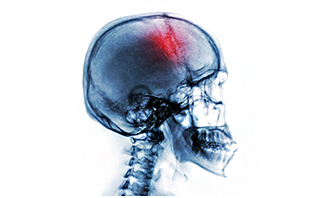

颅骨缺损的发生会出现的症状:

1、颅骨缺损处局部表现:局部有胀痛,缺损边缘疼痛,不能忍受的脑搏动,缺损部高位时头皮向颅内陷入;缺损部低位时,头皮甚至合并部分脑组织,脑室向外膨出。

2、颅骨缺损综合征:主要表现为头痛,头昏,患者对缺损区的搏动,膨隆,塌陷存恐惧心理,怕晒太阳,怕震动甚至怕吵闹声,往往有自制力差,注意力不易集中和记忆力下降;或有忧郁,疲倦,寡言及自卑。

3、长期颅骨缺损:有脑膨出或突出时,脑组织可萎缩及囊变,小儿颅骨缺损随脑组织发育而变大,影响正常脑发育而出现智力偏低;成年人可出现反应迟钝,记忆力下降甚至局灶性神经系统症状,体征,脑膜-脑瘢痕形成时可伴癫痫。

注意:颅骨缺损是颅脑损伤、颅骨骨瘤等开颅术后常见后遗症。当缺损范围直径超过3厘米时,不仅严重影响患者美观,而且会出现多种临床表现如头痛、头晕、情绪改变、缺损区搏动等,甚至可以可能诱发癫痫等严重的疾病,严重影响患者正常的工作和生活。